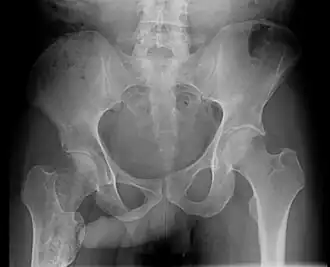

The John Thomas sign,[1] also known as the Throckmorton sign,[2] is a slang or joke term used in the field of radiology. It refers to the position of a penis as it relates to pathology on an X-ray of a pelvis. When the penis (visible on the X-ray as a shadow) points towards the same side as a unilateral medical condition such as a broken bone, this is considered a "positive John Thomas sign," and if the shadow points to the other side, it is a "negative John Thomas sign."[3]

Studies have shown that the "sign" is no better than chance at identifying the location of a hip fracture.[4][5] In those cases where the John Thomas sign is positive, it has been proposed that a person with a displaced hip fracture may try to lie on the injured side to immobilize the fracture and reduce pain; the penis then inclines toward the downward (injured) side.[6]

Andy Murray, British professional tennis player, released a picture of his pelvic X-ray following his hip resurfacing surgery on January 29, 2019,[7] clearly demonstrating an example of a negative John Thomas or Throckmorton sign where his penis pointed away from the site of injury. The release of the X-ray image with visible genitalia was discussed by Piers Morgan on Good Morning Britain, prompting Murray, who was watching at the time, to message the show, stating, "Please can you stop discussing my genitals on national TV, I was heavily medicated at the time of posting."[8]